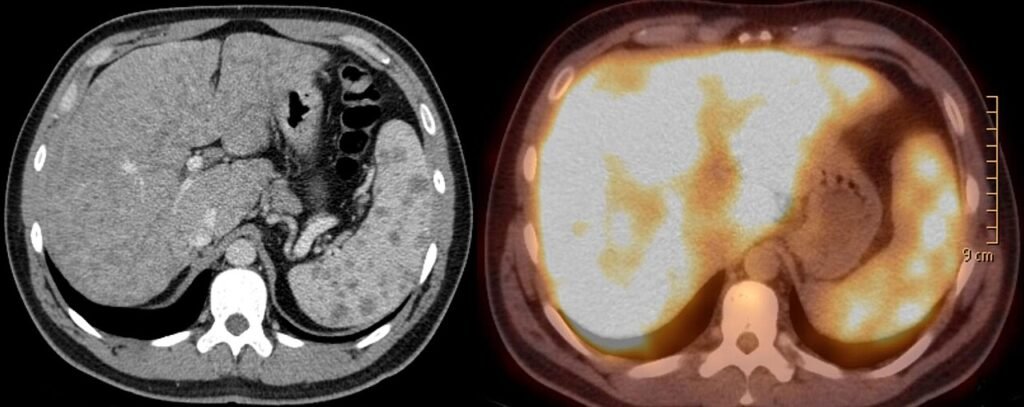

1. Mejoras tecnológicas: los equipos de TC, RM y técnicas híbridas (PET/TC, PET/RM) ofrecen resoluciones mayores, velocidades de adquisición superiores y nuevos biomarcadores de enfermedad.

Fotografía de Hellerhoff – Own work, CC BY-SA 3.0, imagen de sarcoidosis hepática y esplénica – TC axial y PET-TC.